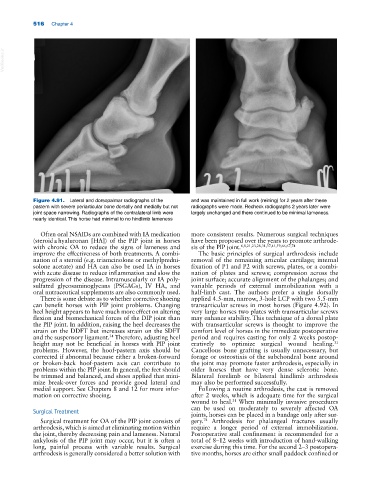

Figure 4.91. Lateral and dorsopalmar radiographs of the and was maintained in full work (reining) for 2 years after these

pastern with severe periarticular bone dorsally and medially but not radiographs were made. Recheck radiographs 2 years later were

joint space narrowing. Radiographs of the contralateral limb were largely unchanged and there continued to be minimal lameness.

nearly identical. This horse had minimal to no hindlimb lameness